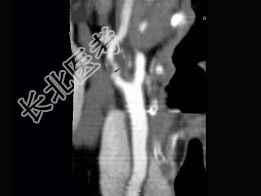

- 多项选择题男,65岁, 近半年时常突发性头晕,CT三维重建如图, 正确的描述或结论是 ( )

A、颈内动脉起始段有一长约3.0cm的狭窄段

B、狭窄段可见低密度不强化血栓影

C、狭窄段管壁见点状致密钙化影

D、拟为颈内动脉粥样硬化性狭窄

E、拟为颈外动脉粥样硬化性狭窄